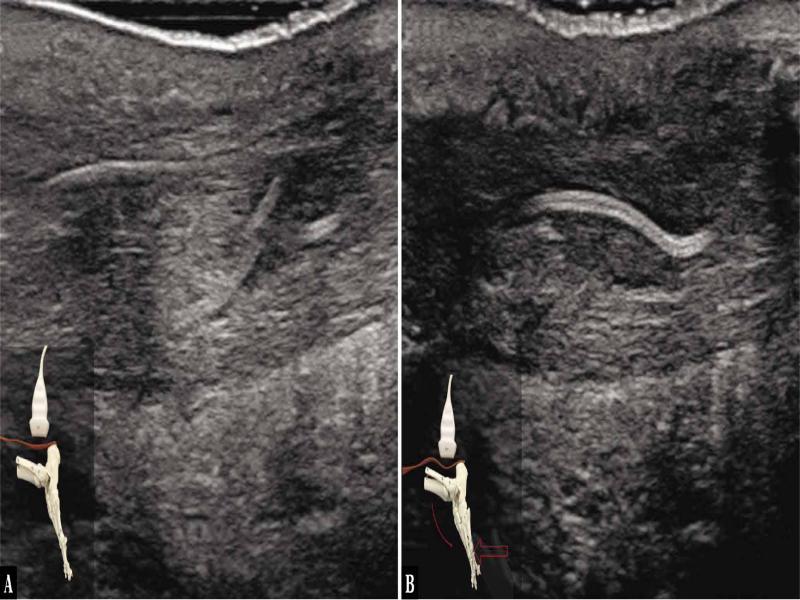

Fig. 3.

![Ultrasound examination protocol. A. The transducer is applied along the AT, above the calcaneal tuberosity. At rest, the tendon is undulated, there is no tension in the AT, which is visible on ultrasound as blurred tendon structure with no linear fibrillar arrangement of the fibres. An abnormal image. B. An 18–5 MHz US image of a tendon during the remodelling phase at 3 months after the surgery. Longitudinal plane, there is no linear arrangement of AT fibres; blurred tendon structure, hypoechoic zones are present within the tendon; the image indicates the absence of resting tension. [red arrows mark the borders of the tendon]](https://sciendo-parsed.s3.eu-central-1.amazonaws.com/64722e23215d2f6c89dbec00/j_jou.2021.0043_fig_003.jpg?X-Amz-Algorithm=AWS4-HMAC-SHA256&X-Amz-Content-Sha256=UNSIGNED-PAYLOAD&X-Amz-Credential=ASIA6AP2G7AKBY2AOJTK%2F20251216%2Feu-central-1%2Fs3%2Faws4_request&X-Amz-Date=20251216T170210Z&X-Amz-Expires=3600&X-Amz-Security-Token=IQoJb3JpZ2luX2VjEJ%2F%2F%2F%2F%2F%2F%2F%2F%2F%2F%2FwEaDGV1LWNlbnRyYWwtMSJIMEYCIQDpGWJy5nYmL6vQIHHt%2BcL%2F3OSMUmRuP2Jq%2F0ZR1%2FLQBwIhAMOCdMyV4r3yYa%2BF%2FudRVaQIR4fmJylEiwzwqN7lTdT5KrwFCGgQAhoMOTYzMTM0Mjg5OTQwIgz4VpTpHrGQ%2BRwhfVIqmQUmdJgnr7B%2F2TCxvDKqjEoGFRsgxmY1WO7B2uHZlmD80cdU17oWnLhWozEmhOcl3%2FA2q7bDkKBAuPcFO1a7dNHauScY2SzHlX0kIwGWBTyagWuMSXxWSKl7tuRn79BzKKKgACwrvnuaElPejVfsbXCLbokYmV3F5d6L7ZvYrBqtQi69XC21CoAlb8Y6i6%2FgGjbHb96ZBwCqvP7cOXSUTpBBNcWXDb3SBoKgMOvVGHUg3rSkHFBWbeUJWEqFQuQLNZGIPzAiqdGcNpaQoxwYfz5gf2hRAObi1TmBBQCJk0SxpwaFBWoacduWkTQZ5HNbLbV2Y7aFE3mDRSzYCiCfLMQh7Mgepw0nBxMmfE85hi32y%2BHl0YbHclUDfuc6cLW%2FYcTSrFNW5DY1zlMhrYkTdcHwhlV1hhIJTQNjAopybRxyhl8UYT%2FarnBEwsCeDtNSkjr%2BbyoA4Mb304CzPuGRdqK9emQVbV5UYjlPpV4HDHxB%2Feh%2FvM4JIZO4n8g6cp3NqtH4DmY0IW9MSRtklWQp1NGIx%2FvKjGOq7aOzqrJapYKvKLlD5e4RXY6v%2FiOPFbAdlTfn5%2FqC4BWLoxMGssJ9k0H38JHeskVYSwPhVqIo0EtaUeEaKSM06dRorQWA4zp9F2C8ovAo54ubZDzgUdOR0AQTvRjPzuFLiqLDfhn7QV8H0gLPqSM190VJgPIW5IZZPui4U7%2FBneLPSyQBM0j6QtUb8Mst%2FeYnWZLJMIdEPA%2Bv6au%2BzISiEhwEeyP69vVeq%2B5DRurxZDk6yvkPWt7OPS0VcMYYkMEE%2FBKpoOMCHV5smh95YG7YQar4J%2FuRfCRSBakAngbpy9rbUzTx0nincY30w2DOtdkRQ%2B6llm11f5dKO2lDvaYDR9zwsjDY3YXKBjqwAWriJvfX%2BElci0gwZQievDMAbkmHC4QI%2FqxewR1beknZpaCkRtCONkVDPkjy%2BT4qSFomaXZUpQZ4%2FUCmLMIxbgvXVx2C%2F8RvVqLErXggh0KomRU%2B0YjqHSFLW6f4wXhBudqG47DjGNdcJofTT2PytMHHltz%2Fhgs2cVWnTfkhMiVrxvUgXovn9cYHmefQfFeOjU7b7EZJzwNBhn624LDbKUNBrlDn2%2FKsMwkUHsc1t%2Flz&X-Amz-Signature=7b88cbb8c94f6d14a36218da133669c2cf020c2f4ff3ae5195e2b2f0de3badbf&X-Amz-SignedHeaders=host&x-amz-checksum-mode=ENABLED&x-id=GetObject)